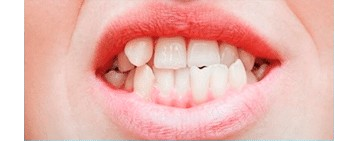

Los dientes inferiores están en el exterior (hacia adelante) cuando muerde.

Posicionamiento inadecuado de los dientes.